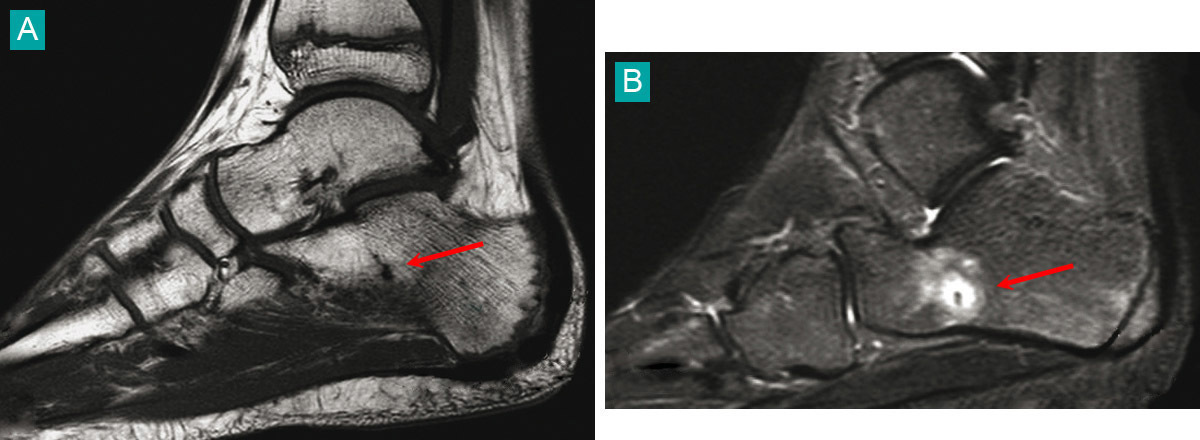

Fracture de fatigue du calcanéum sous forme d'une ligne fine en hyposignal sur les séquences T1 (A), et se rehaussant sur les séquences injectées (B). Voir : P. Journeau, E. Polirzstok, F. Launay, D. Barbier. Lésions osseuses de sollicitation excessive chez l’enfant sportif. Rev Prat 2015;65(8);1084-90.